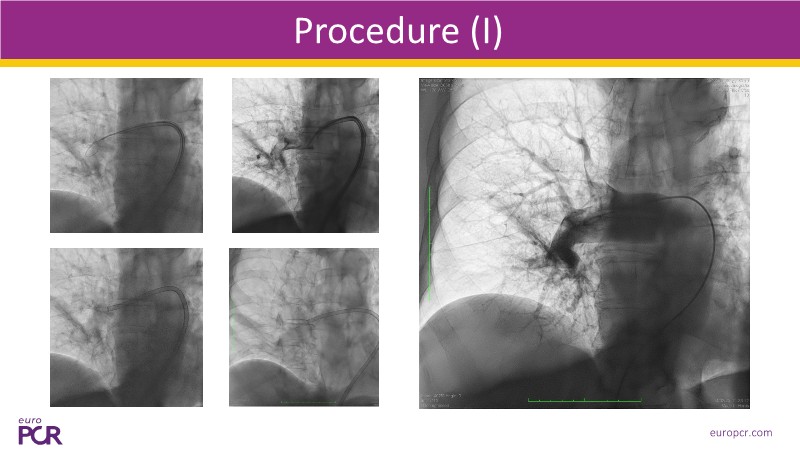

Watch this EuroPCR 2025 session on pulmonary embolism to explore the role of computer-assisted vacuum thrombectomy (CAVT) as an alternative to medical treatment in high-risk (massive) PE, supported by insights from the STRIKE PE study. Discover how CAVT rapidly and effectively offloads the right ventricle in intermediate-high-risk PE patients, especially those with a high bleeding risk. Review safety and efficacy data from a cohort of 450 patients demonstrating consistent procedural success. In short, this video provides a clear understanding of key procedural considerations, the latest evidence on Penumbra technology, and how ongoing innovation is shaping the future of PE management.